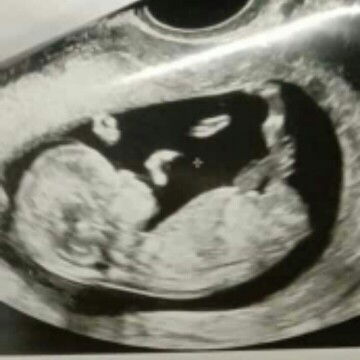

Queen of 3 adventurous cub